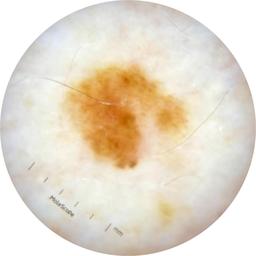

ISIC_6708537

Information

2077 x 2077

Clinical

Field Value

acquisition_day 525

age_approx 70

anatom_site_1 Upper extremity

anatom_site_general upper extremity

concomitant_biopsy False

diagnosis_1 Benign

diagnosis_confirm_type single image expert consensus

family_hx_mm False

fitzpatrick_skin_type I

image_manipulation instrument only

image_type dermoscopic

lesion_id IL_6558300

patient_id IP_3297880

personal_hx_mm True

sex female